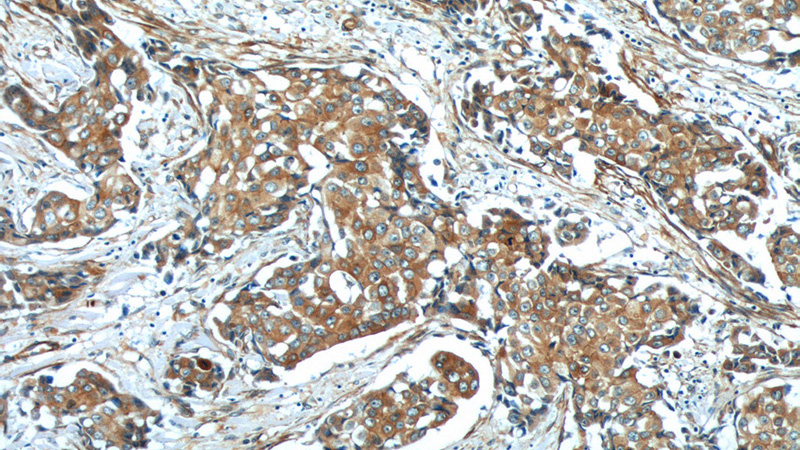

Immunohistochemistry of paraffin-embedded human breast cancer tissue slide using Catalog No:109154(CDH26 Antibody) at dilution of 1:50 (under 10x lens)

Immunohistochemistry of paraffin-embedded human breast cancer tissue slide using Catalog No:109154(CDH26 Antibody) at dilution of 1:50 (under 40x lens)